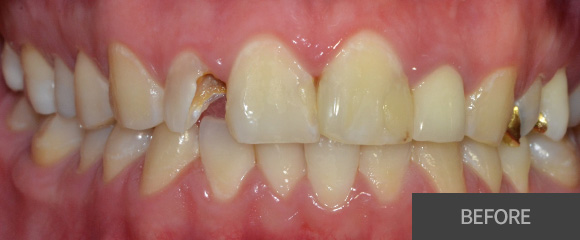

충치치료

레진

인레이

크라운